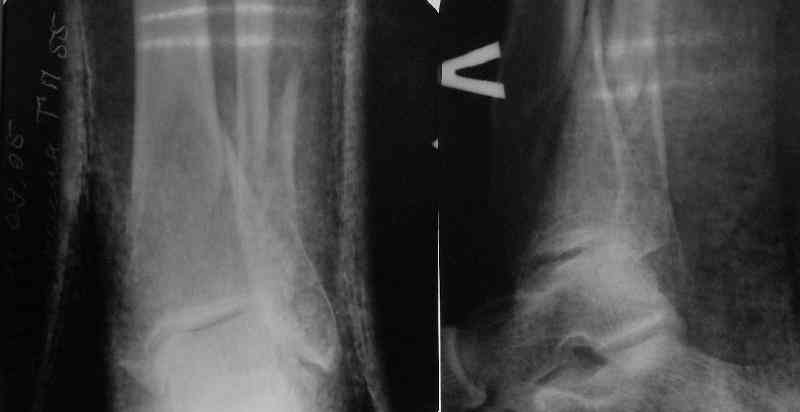

In delayed cases acute length restoration performed only in the tibia may leave the fibula shortened thus change the mortise. So it is reasonable to restore length of both bones simultaneously by distractor and fix the fibula not with open reduction and plating but just by a single perQ screw. Example attached.

At least both the ankle mortise and tibial alignment look acceptable, don't they?

I am just trying to illustrate that prevention of 1)tibial valgus and 2)loss of reduction can be provided without fibular plating. Small changes of conventional nailing techniques allow to maintain reduction of the tibia reliably without adjunctive fibular stabilization.